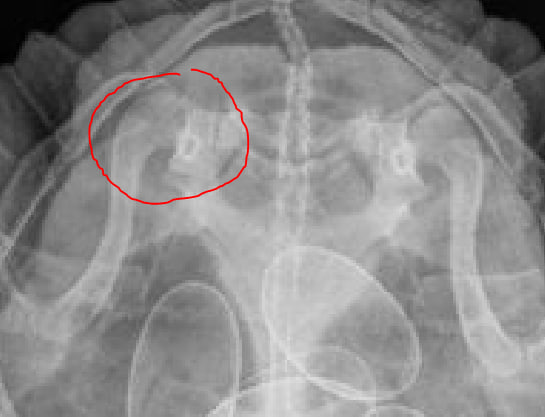

NataLiRED Ваше имя: Наталья Локация: Арзамас, РФ Опубликовано: 27 апреля 2023 Автор Опубликовано: 27 апреля 2023 Мы таки сходили в вет клинику. Взвесила ее там - 2,80 кг. И, собственно, сам рентген. 8 яиц. Одно какое-то интересненькое. Подозреваю, что сегодняшнее яйцо вышедшее упирало другие яйца в лапу как раз в правую. В клинике сейчас ходила без хромоты, как мне показалось.

Консультанты moth Ваше имя: Мария Локация: Москва Опубликовано: 29 апреля 2023 Консультанты Опубликовано: 29 апреля 2023 @NataLiRED врач ответила также, что нужно дождаться всей кладки. По рентгену только если вот это место похоже на подвывих тазобедренного сустава, но опять таки надо смотреть после кладки